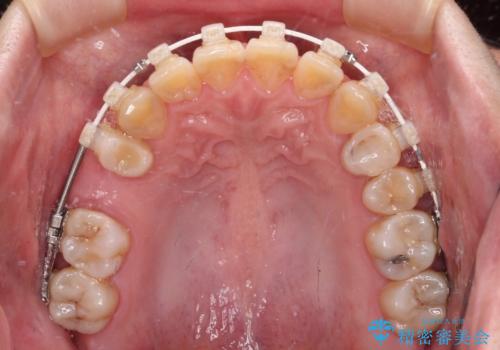

- 奥歯に問題が多くて困っているとのことで来院された患者様です。

開咬により奥歯のみが接触している状態で、前歯部にほとんど接触のない状態で、奥歯に非常に負担のかかる咬み合わせでした。

また、欠損や根管治療の必要な歯など、むし歯による問題も多く散見されました。

まずはむし歯の治療を行い、その後ワイヤー矯正にて咬み合わせを改善し、途中インプラント埋入を行い、矯正治療後に補綴治療を行うこととしました。